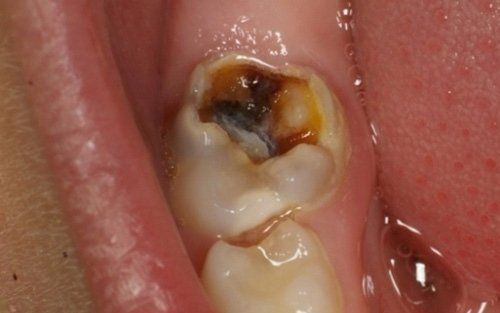

La carie nel bambino è una delle principali cause, insieme all’ortodonzia, di richiesta di intervento del dentista. La patologia ha una evoluzione particolarmente rapida in virtù della scarsità di smalto a difesa del dente da latte. Ciò comporta che, dal momento in cui il dente si ammala a quello in cui ne viene coinvolta la polpa (ovvero il nervo), il tempo sia veramente poco (vedi anche endodonzia pediatrica).

Spesso i dentini da latte cominciano a cariarsi già appena erompono nel cavo orale in quanto sono frequentemente a contatto con zuccheri semplici, come quelli veicolati dal biberon. Particolarmente aggressivi per i denti da latte risultano: tutte le tisane/infusi in commercio in bustine già pronte e pre-zuccherate; il latte zuccherato con qualsivoglia tipologia, incluso il miele; il latte e biscotti, specie nell’uso notturno; l’utilizzo quotidiano, spesso al posto dell’acqua, di succhi di frutta o bevande acide, per citare alcuni fra i più comuni errori commessi nel tentativo di dare una alimentazione completa al bambino, che spesso si traduce nella comparsa di una patologia chiamata